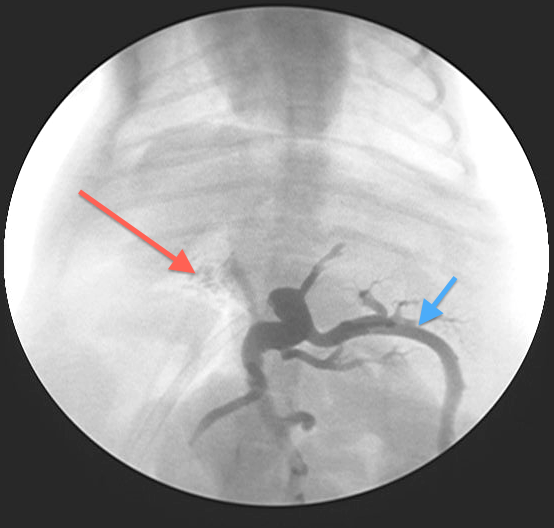

Fig 4:

Portovenogram following test ligation (temporary complete occlusion of the PSS) – most contrast has backed up through the splenic vein (blue arrow) with only some contrast going through the right portal vein into the liver (red arrow). This patient would not tolerate complete ligation of the shunt

Most animals cannot tolerate complete ligation at the time of surgery as the portal circulation is usually relatively under-developed and unable to cope with the increased blood flow. This would lead to portal hypertension which can be rapidly fatal.

PSS’s in animals unable to tolerate complete occlusion are therefore gradually attenuated by placement of either an Ameroid Constrictor or Cellophane Band around the shunt allowing gradual reduction of the shunt and simultaneous development of the portal vasculature in response to the increased blood flow.